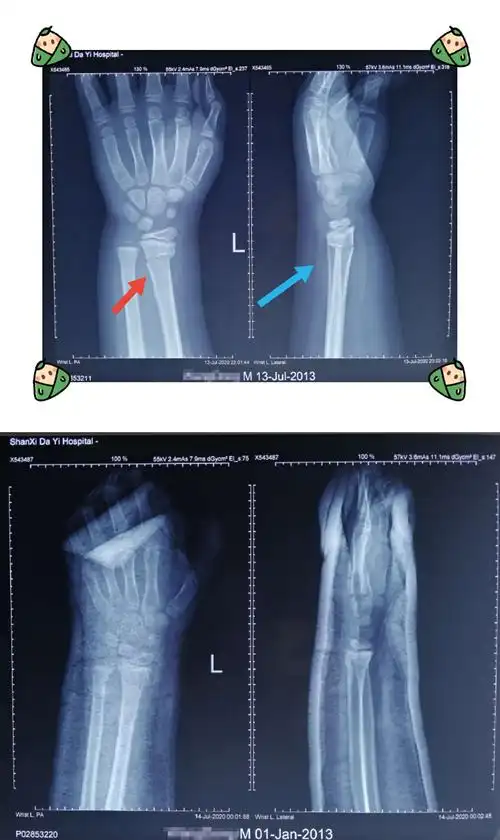

男孩,7岁,左桡骨远端骨折